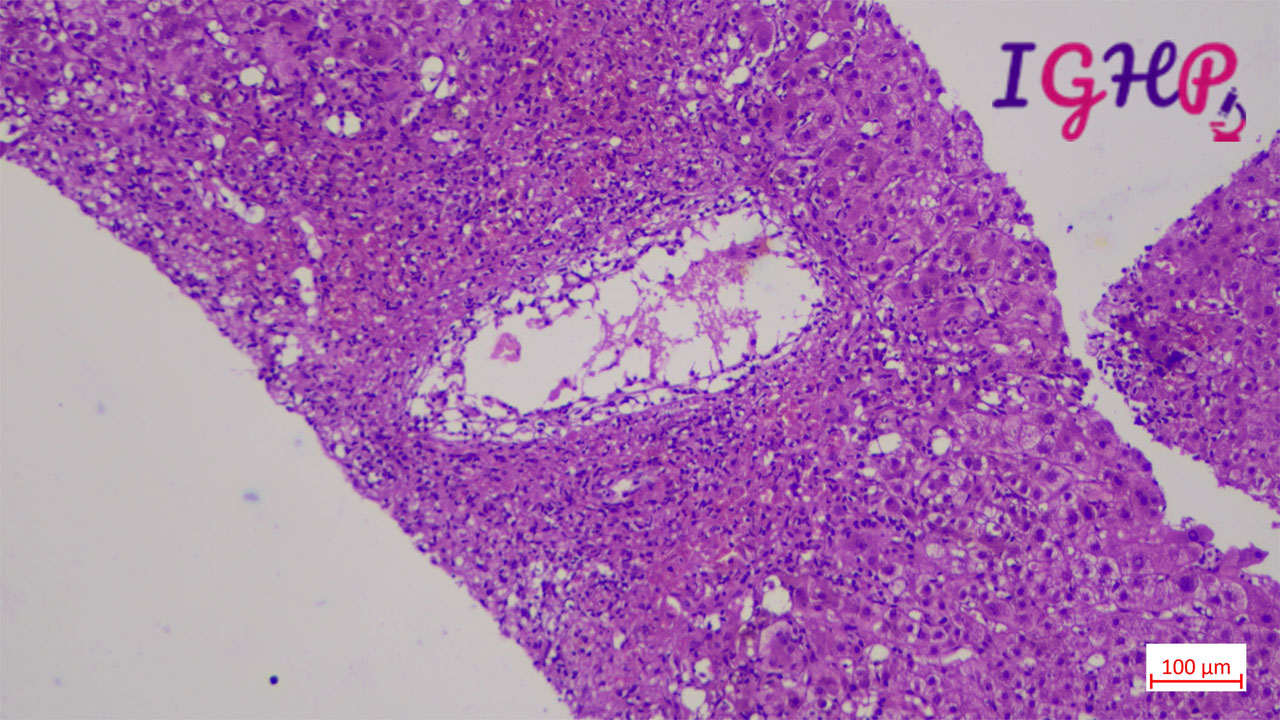

Microscopic Images-

Microscopic examination showed an areas of perivenular hepatocyte loss with prominent central perivenulitis.